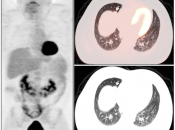

Lung Nodule Identification:

NAC images can occasionally be useful in identifying mild to moderately FDG-avid lung nodules, especially those located in the lung periphery or lung bases.